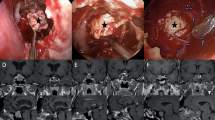

Binary logistic regression analyses identified two variables that reached statistical significance in predicting histological invasion: Knosp grade and pituitary adenoma subtype (Table 3). Tumors with a Knosp grade >2 (OR 50.04, CI 29.01-111.23, p=0.0002) and somatotroph adenomas (OR 20.6, CI 2.55-167.88, p<0.05) were highly predictive of histological invasion. Neither gender (OR 2.46, CI 0.83-7.3, p=0.11), tumor size (OR 1.00, CI 0.95-1.07, p=0.69) nor functional status of the tumor (OR 1.27, CI 0.14-12.00, p=0.83) achieved statistical significance in our analysis and therefore did not predict cavernous sinus medial wall invasion (Table 3). Figure 2 demonstrates case examples of different pituitary adenomas with varying preoperative Knosp grades as well as the same Knosp grade demonstrating differential patterns of invasion into the medial wall of the cavernous sinus.

We hypothesized from our intraoperative experience with pituitary tumors that some pituitary adenoma subtypes have a predilection for invading the medial wall of the cavernous sinus more so than others. Case examples of various pituitary adenomas with varying Knosp grade and invasion into the medial wall of the cavernous as viewed on preoperative MRI (T1 with gadolinium), through medical illustrations, from an endoscopic intraoperative view, and microscopically with histological H&E staining and immunocytochemistry. (A) Preoperative coronal MRI demonstrating a Knosp grade 1 corticotroph adenoma (B) A medical illustration of the intraoperative view from an endoscopic transsphenoidal approach after the adenoma has been removed and the pituitary gland remains displaced the left side of the field exposing an intact medial of the cavernous sinus with no evidence of invasion (C) An intraoperative view from an endoscopic transsphenoidal approach after the adenoma has been removed and the pituitary gland remains displaced the left side of the field exposing an intact right medial wall of the cavernous sinus with no evidence of invasion (D) Histological images of H&E slides of a resected medial wall with no evidence of invading pituitary adenoma cells (E) Histological images of immunohistochemistry slides of a resected medial wall with no evidence of invading pituitary adenoma cells (staining for T-pit transcription factor) (F) Preoperative coronal MRI demonstrating a Knosp grade 1 somatotroph adenoma (G) A medical illustration of the intraoperative view from an endoscopic transsphenoidal approach after the adenoma has been removed and the pituitary gland remains displaced to the left side of the field exposing the right medial wall of the cavernous sinus with subtle evidence of tumor invasion (H) An intraoperative view from an endoscopic transsphenoidal approach after the adenoma has been removed and the pituitary gland remains displaced the left side of the field exposing the right medial wall of the cavernous sinus with subtle evidence of tumor invasion (I) Histological images of H&E slides of the resected medial wall with evidence of invading pituitary adenoma cells (J) Histological images of immunohistochemistry slides of the resected medial wall in the case with evidence of invading pituitary adenoma cells (staining for Pit-1 transcription factor) (K) Preoperative coronal MRI demonstrating a Knosp grade 3 somatotroph adenoma (L) A medical illustration of the intraoperative view from an endoscopic transsphenoidal approach after the adenoma has been removed and the pituitary gland remains displaced to the left side of the field exposing the right medial wall of the cavernous sinus with frank evidence of tumor invasion (M) An intraoperative view from an endoscopic transsphenoidal approach after the adenoma has been removed and the pituitary gland remains displaced the left side of the field exposing the right medial wall of the cavernous sinus with frank evidence of tumor invasion (N) Histological images of H&E slides of the resected medial wall in this case with evidence of invading pituitary adenoma cells O. Histological images of immunohistochemistry slides of the resected medial wall in this case with evidence of invading pituitary adenoma cells (staining for Pit-1 transcription factor).